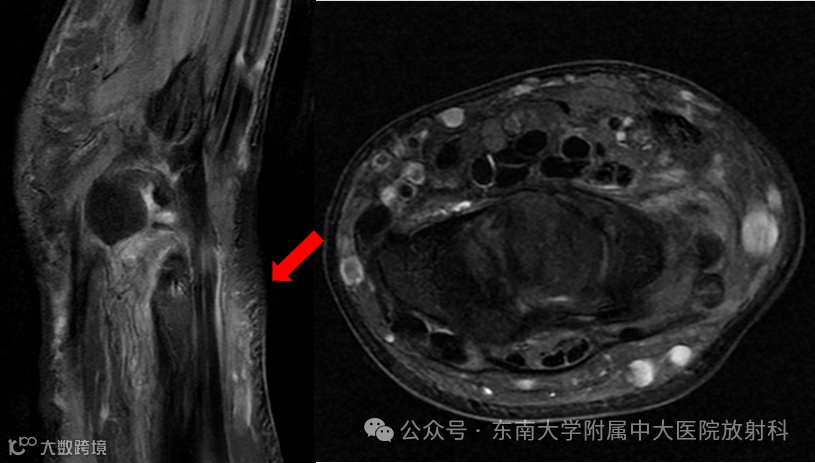

病例1

男 ,17岁

主诉:被撞伤致左腕关节肿痛半小时

病史:约半小时前患者骑车时被撞倒地,致右肘、左腕、双侧膝关节多处皮肤擦伤伴局部肿痛,受损关节活动稍受限,前来就诊

专科检查:左腕关节肿胀,局部压痛,左腕关节活动稍受限

影像号:3557176,2025-12-09,左腕关节正侧位X线、左腕关节CT平扫;影像号:3559976,2025-12-13,左腕关节MRI平扫

影像学表现